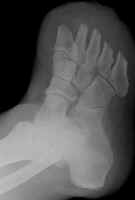

Another transmetatarsal amputation.